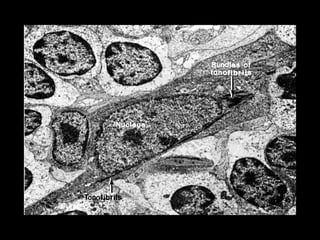

 •• Birbekove granuleBirbekove granule

 •• Brojni nastavci tj.Brojni nastavci tj.

DendritiDendriti

 MHC IIMHC II

Antigen-prezentujuće ćelijeAntigen-prezentujuće ćelije (APC)(APC) Makrofagi,LangerhansoveMakrofagi, Langerhansove ćelije, dendritične,ćelije, dendritične, folikulodendritične,folikulodendritične, interdigitatne, M ćelije,interdigitatne, M ćelije, epitelne retikularneepitelne retikularne ćelije timusa i Bćelije timusa i B limfocitilimfociti  •• Birbekove granuleBirbekove granule  •• Brojni nastavci tj.Brojni nastavci tj. DendritiDendriti  MHC IIMHC II